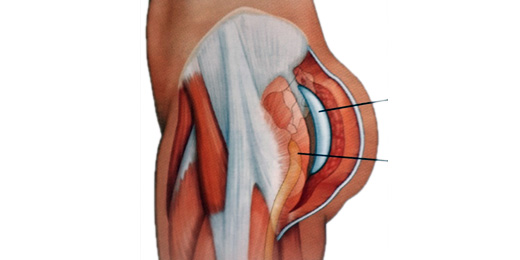

Los planos de colocación que existen son: subcutáneo, subfascial, retromuscular e intramuscular.

El plano subcutáneo presenta un alto índice de complicaciones como seroma, contractura capsular e implante visible y palpable, por lo que no se utiliza actualmente.

El plano subfascial se utiliza en casos seleccionados, que presenten buen panículo adiposo para evitar la visibilidad del implante.

El plano retromuscular es una buena opción, pero permite sólo la inclusión de implantes pequeños, ya que no deben sobrepasar el límite del músculo piramidal para no comprometer el nervio ciático.

El plano intramuscular se considera el más adecuado actualmente, ya que permite cubrir totalmente el implante, pudiéndose utilizar implantes de mayor tamaño y forma anatómica.

Este plano es el que brinda los resultados más naturales.